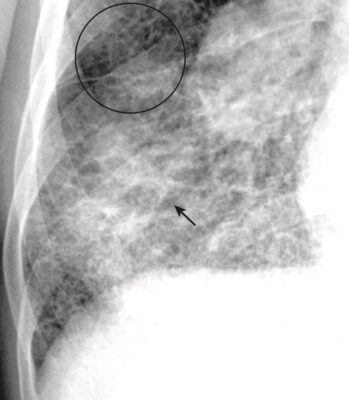

- Cạm bẫy: Đôi khi có bệnh kẽ dày đặc đến nỗi các thành phần của bệnh có thể chồng lên nhau và trông có vẻ như bệnh khoang chứa khí trên phim X quang ngực thông thường. Hãy nhớ rằng hình ảnh X quang thường quy là biểu diễn hai chiều của vật thể ba chiều (con người), vì vậy, tất cả các đậm độ trong phổi đều bị xếp chồng lên nhau trên bất kỳ một góc chụp nào. Điều này có thể làm cho các phần tử nhỏ của bệnh kẽ dường như dính liền lại và giống bệnh khoang chứa khí hơn.

- Giải pháp: Nhìn vào vùng ngoại vi của các bóng hội tụ (confluent shadows ) đó để xác định xem chúng thực sự là do bệnh khoang chứa khí hay do sự chồng lên của nhiều dạng lưới và dạng nốt (Hình 10).

- Chụp CT ngực để xác định rõ hơn đặc điểm của bệnh.